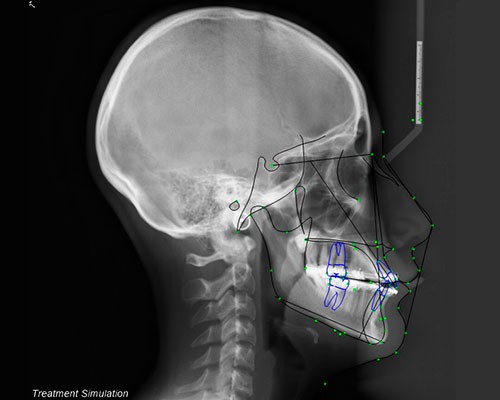

SISTEMAS DIGITALES 3D